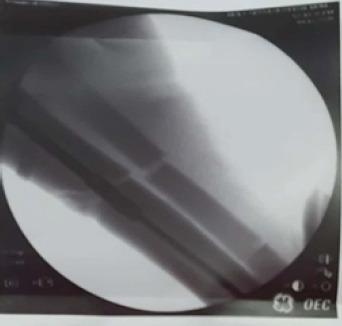

A 26-year-old male patient had road traffic accident and sustained a close fracture of the right distal 3rd tibia along with segmental fracture of the adjacent fibula. The tibia nailing was done under combined spinal and epidural anesthesia. The proximal tibia was approached by a midline incision with splitting of the patellar tendon. The reduction of the fracture fragments was done and the guide wire was inserted. The medullary canal was narrow and hence the initial reaming was started with the smallest available, that is, 8 mm reamer. After crossing the fracture site, we noticed that reamer coiled shaft got broken into multiple pieces in the medullary cavity at proximal 3rd tibia. The fracture site was exposed and a linear osteotomy was done in distal tibial fragment. Through this window, the broken reamer was pushed in the retrograde manner and was delivered out. Most of the broken metal pieces of the reamer shaft were removed with pituitary rongeur. An 8 mm solid IM nail was passed in antegrade manner across the fracture site and was locked distally and proximally. The operative wounds were irrigated and closure was done in layers. The patient was allowed partial weight bearing at 3 weeks post-surgery with gradually progressing to full weight bearing at 10 weeks after confirming clinical and radiological union.

一名26岁男性患者遭遇道路交通事故,导致右胫骨远端三分之一处闭合性骨折,同时相邻腓骨出现节段性骨折。在腰麻联合硬膜外麻醉下进行胫骨钉固定。经髌腱正中切口显露胫骨近端。对骨折碎片进行复位并插入导丝。髓腔狭窄,因此最初使用最小号的扩孔钻,即8毫米扩孔钻开始扩孔。穿过骨折部位后,我们注意到扩孔钻的螺旋轴在胫骨近端三分之一的髓腔内断成多段。显露骨折部位,在胫骨远端碎片上进行线性截骨。通过这个窗口,将断裂的扩孔钻逆行推挤并取出。用咬骨钳取出了扩孔钻轴的大部分断裂金属碎片。一枚8毫米实心髓内钉顺行穿过骨折部位,并在远近端锁定。冲洗手术伤口并分层缝合。术后3周允许患者部分负重,在确认临床和影像学愈合后,逐渐在10周时过渡到完全负重。